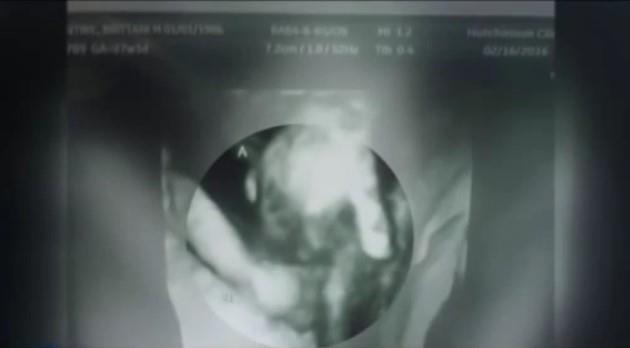

(VIDEO) DOKTORI SU REKLI DA JEDAN BLIZANAC NEĆE PREŽIVETI: Onda je ultrazvuk pokazao čudo...

Međutim, ubrzo su stigle loše vesti. Naime, doktori su otkrili da jedna beba verovatno neće da preživi zbog deformacija na srcu i mozgu.

Operaciju je bilo moguće izvesti, ali je rizik bio prevelik. Onda se početkom sedmice dogodilo nešto neverovatno. Nažalost, nije to nešto što će povećati šansu dečaku da preživi, ali je prizor koji doktori retko imaju priliku da vide.

Svoju snažniju sestru, dečačić je držao za ruku. Kao da želi da ga ona zaštiti, da mu pomogne...